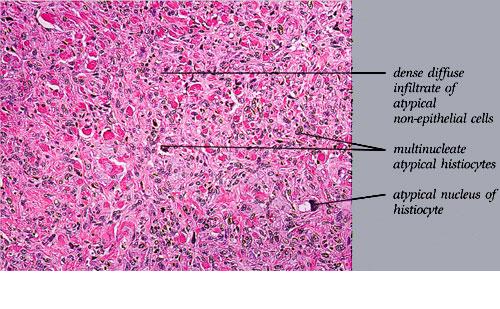

malignant-fibrous-histiocytoma